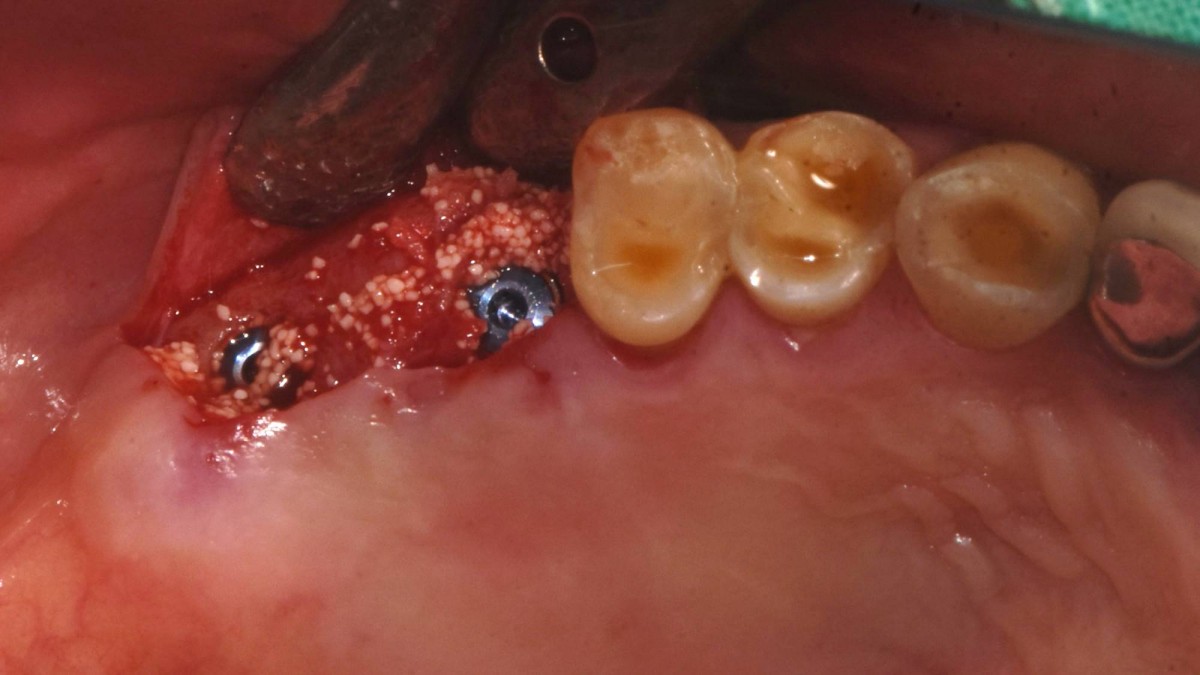

Socket Lift and Implant Placement in the right maxilla.

<GCacg> A 56-year-old male patient complained of pain in the right upper and lower jaws. And he wanted the upper first molar to be pulled out first.